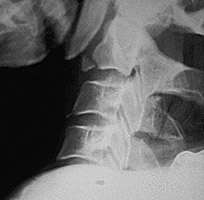

Extension Teardrop Fracture

A stable injury, this fracture results from severe hyperextension and results in avulsion of the anterior inferior corner of a vertebral body, typically C2. The teardrop fragment is avulsed and is attached to the anterior longitudinal ligament.

- Click on the image for a larger versionALateral radiograph of the cervical spine. This fracture from the anterior inferior corner of C2 resulted from severe hyperextension.